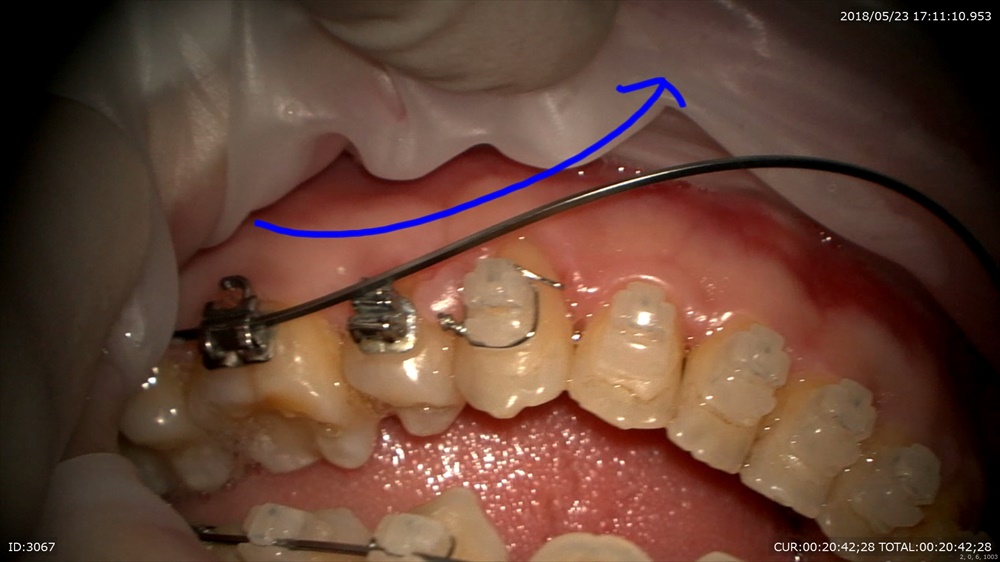

今日のケース。前歯のリトラクションが終了。その反作用でかみ合わせが若干深くなっています。

湾曲がこんな感じ。

そこでこのようなワイヤーをIN。トルクもIN

パッジブタイバックも忘れずに。スペースが開いてしまわないように。

マイクロスコープで観察することでトルクの入れ具合が顕著に解る!!